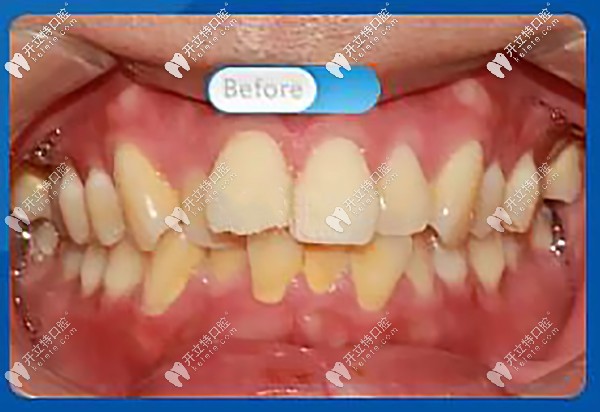

托槽矯正前,正面看牙齒屬于重度擁擠,微笑時(shí),明顯看到前牙凸出,凸嘴齙牙明顯

正面看牙齒屬于重度擁擠

醫(yī)生:“從口內(nèi)正面照可以看到上牙列前牙前突,上下牙列不齊擁擠,牙中線不齊,上下咬合不協(xié)調(diào),磨牙深覆蓋。”

磨牙深覆蓋